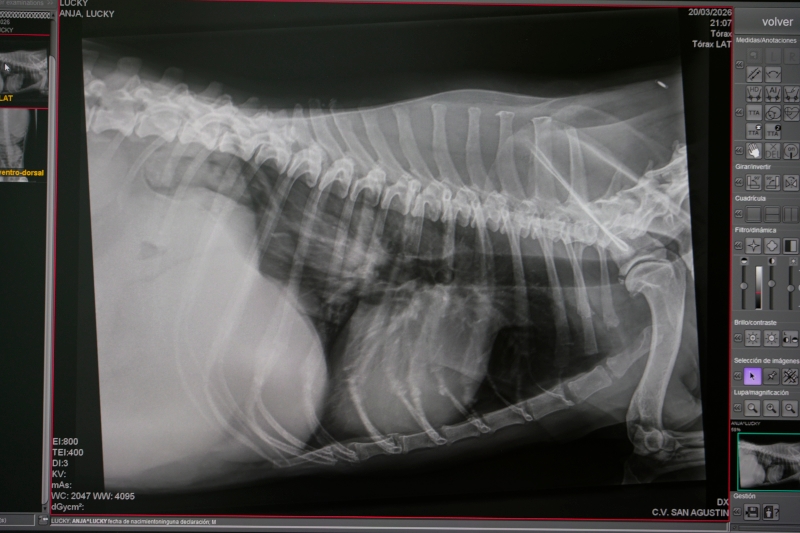

Radiología para salir de dudas

Hay veces que una exploración física no es suficiente, y hace falta una radiografía para confirmar/descartar un diagnóstico.

De nuevo, esto no se hace por capricho. Si se realiza, es porque realmente lo necesita.